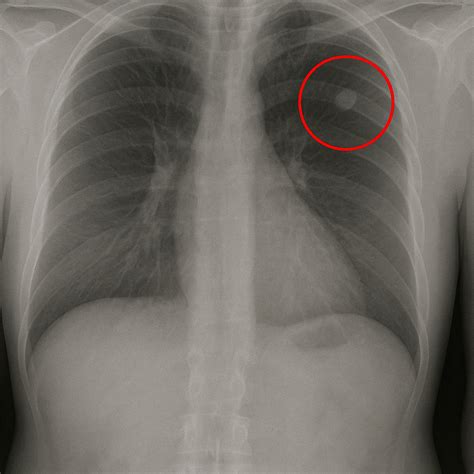

• Chest X-ray: This is often the first step in detecting lung nodules, but it has limitations in terms of detail and sensitivity.

When evaluating pictures of lung nodules, radiologists look for specific characteristics that can indicate the nature of the nodule. These characteristics include:

• Size: Larger nodules are more likely to be malignant.

• Shape: Irregular or spiculated edges are often associated with cancer.

• Density: Solid nodules are more concerning than ground-glass nodules.

• Growth Rate: Rapidly growing nodules are more likely to be malignant.